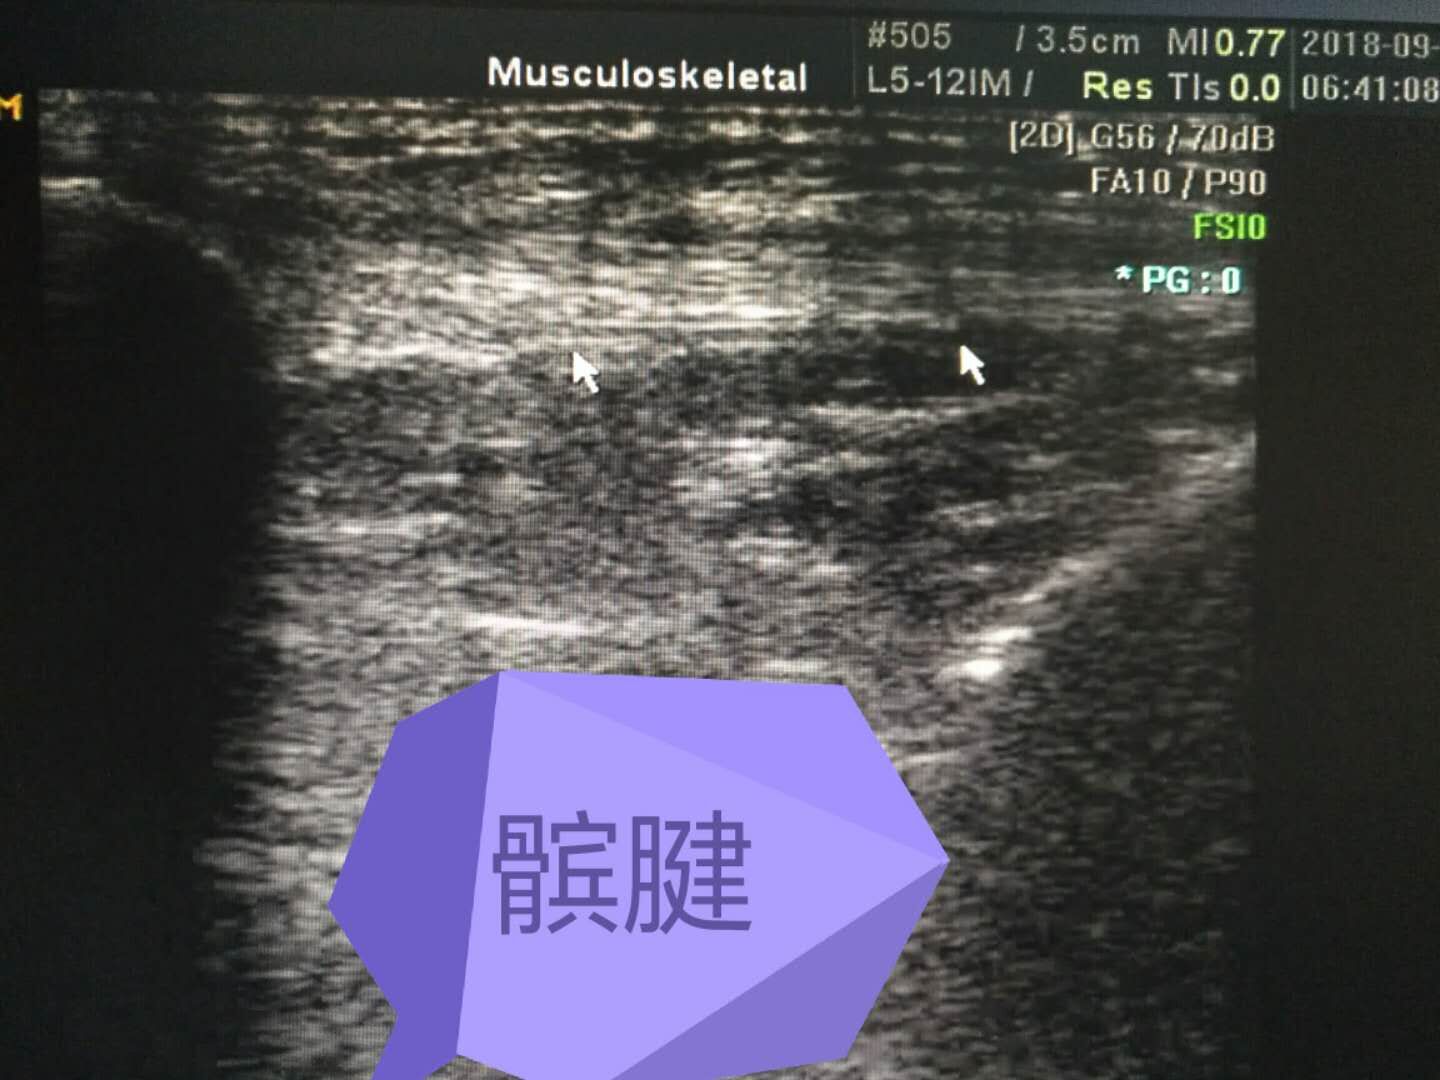

髕腱

科室專(zhuān)業(yè)特色:產(chǎn)科四維、腔內超聲、胃超聲、肌肉、肌腱、關(guān)節、外周神經(jīng)超聲等。優(yōu)勢:無(wú)創(chuàng )、無(wú)輻射、實(shí)時(shí)、便捷。